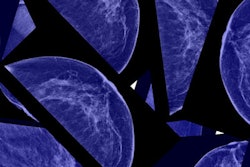

Which factor -- screening or treatment -- has been behind the sharp reduction in breast cancer mortality over the past several decades? A new study published January 9 in the Journal of the American Medical Association found that the answer is simple: both.

Researchers found that the combination of advances in mammography screening and improvements breast cancer treatment reduced breast cancer mortality by 49% in 2012, compared with the number of deaths that would have occurred with no screening and no treatment. While the contributions of screening and treatment have shifted over the years, both have had a major positive effect in the fight to save women's lives.

Breast cancer mortality has fallen over the past several decades in most developed countries that have implemented population-based breast screening. In the U.S., for example, the American Cancer Society's annual report on cancer released this month showed that the mortality rate from female breast cancer fell 39% from 1989 to 2015.

In a 2005 study to which Plevritis contributed, researchers found that screening mammography and breast cancer treatment contributed equally to the reduction in breast cancer mortality from 1975 to 2000 (New England Journal of Medicine, October 27, 2005, Vol. 353:17, pp. 1784-1792). With the current work, Plevritis and colleagues from multiple centers wanted to analyze the effect since 2000 of recent changes in both mammography technology and treatment protocols on mortality rates.